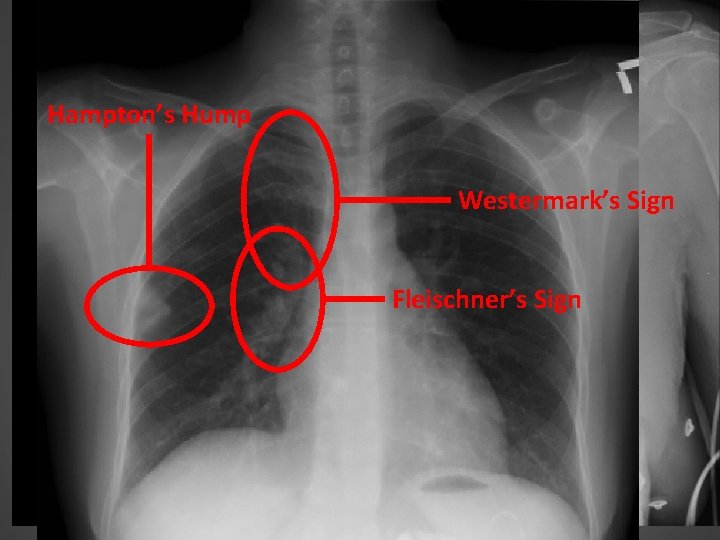

DIAGNOSIS OF PE – CXR Hampton’s Hump abnormal CXR in 84% in PIOPED e. g. atelectasis, pleural effusion Westermark’s Sign main role of CXR is to rule out alternative or coexisting pathology e. g. pneumothorax Fleischner’s Sign assist in determining suitability for V/Q